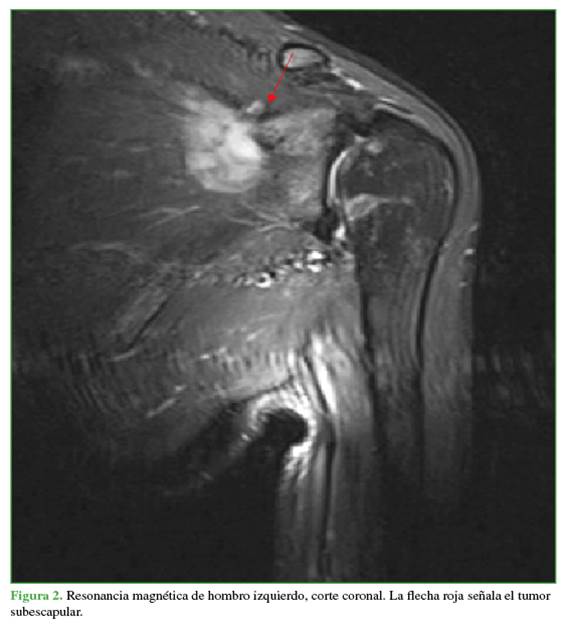

Mujer de 28 años, con antecedentes de escoliosis idiopática del adulto y con un trabajo activo que implicaba la carga de material. Fue derivada a consultas externas de traumatología por omalgia izquierda postraumática de ocho meses de evolución y limitación para la rotación externa, contractura y dolor a nivel del trapecio, sin mejoría tras la rehabilitación. En el examen físico, se detectó hipotrofia relativa de la musculatura escapulohumeral izquierda en comparación con la contralateral. No se palparon masas ni se observaron signos inflamatorios. La movilidad activa y la pasiva estaban conservadas, a excepción de una rotación externa de 0º para el hombro izquierdo y de 75º para el hombro derecho. Asimismo, se constató una discinesia escapulotorácica compatible con una escápula alada izquierda, por lo que se le solicitaron diferentes estudios complementarios. Con la tomografía computarizada, se descartó una enfermedad ósea. En la electromiografía, se detectó una lesión del nervio torácico largo, con características crónicas y de intensidad moderada, lo que impedía la movilidad de la escápula. Además, la resonancia magnética reveló una lesión en el músculo subescapular de unos 5 cm, con bordes pobremente diferenciados, discreta heterogeneidad y ligera hiperintensidad de la señal potenciada en T2, compatible con un proceso fibromatoso (Figuras 1 y 2).